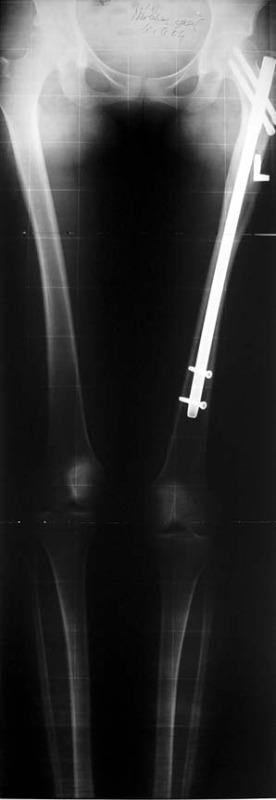

Kombine Boy Uzatma Tekniği (LON: Lengthening Over Nails)

Hem kemiğin içine hem de bacağın dışına cihaz yerleştirilerek ortalama 2 - 3 ay boyunca uzatma işlemi yapılır. 3 aydan sonra bacağın dışındaki bölüm çıkarılır. Kemiğin içindeki intramedüller çivi, kemik tam olarak kaynadıktan sonra istenirse ek bir operasyonla çıkarılabilir. Tek seansta ortalama 6 – 7 cm’lik uzama sağlanır. Hem alt hem de üst bacağa işlem uygulanırsa tek seferde 10 – 14 cm’lik uzatma mümkündür.